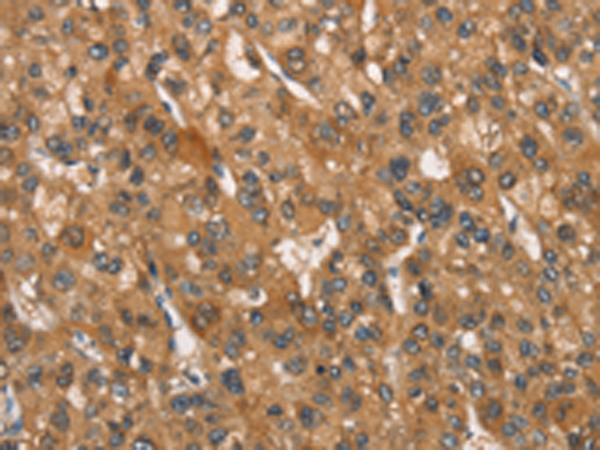

分类: 科研抗体货号: P11208别名: CAE; CAE1; CX50; CZP1; MP70; CTRCT1应用: IHC反应种属: Human, Mouse, Rat